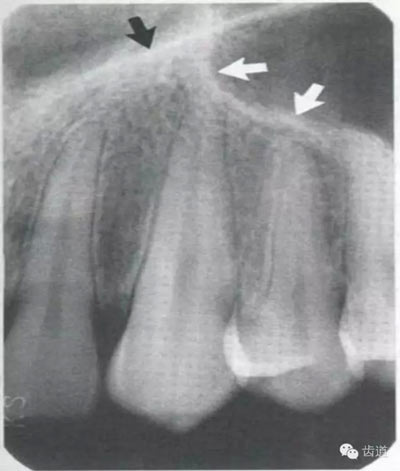

牙頸部Burnout征象:有時因投照技術(shù)問題而造成牙頸部近中或遠(yuǎn)中呈低密度影像,位于牙釉質(zhì)和牙槽嵴頂之間。

在兩個中切牙牙根之間或稍上方,多呈橢圓形密度低的影像,切牙孔影像可重疊在一側(cè)中切牙牙根尖處,易誤認(rèn)為根尖周病變,可視牙周膜和骨硬板是否完整加以鑒別

位于兩側(cè)中切牙牙根之間,由牙槽突向上,呈直線狀密度低的影像。其兩側(cè)為密度高的影像,為兩側(cè)上頜骨腭突的致密骨層。

鼻腔位于上切牙根尖的上方,顯示為對稱性半圓形密度低的影像,其中間被一密度高的骨隔分開為鼻中隔